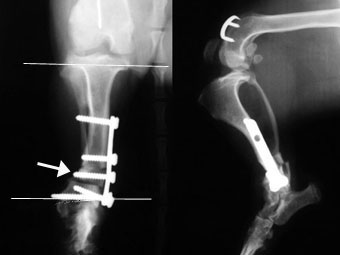

写真3段目: 手術後

足首に近い部分で骨を楔形(外側が厚い)に切り取り、その骨片を(厚い部分が内側になるように)反転して組み込み(白矢印)、骨プレートと骨スクリューで固定しました。膝の関節ラインと足首の関節ラインはほぼ並行に補正できました。